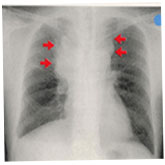

肺がんのレントゲン写真   肺がんの気管支鏡所見

肺癌のレントゲン写真

(65才男性 1日40本 40年間)

右肺上葉から縦隔にかけて巨大な腫瘍を認める